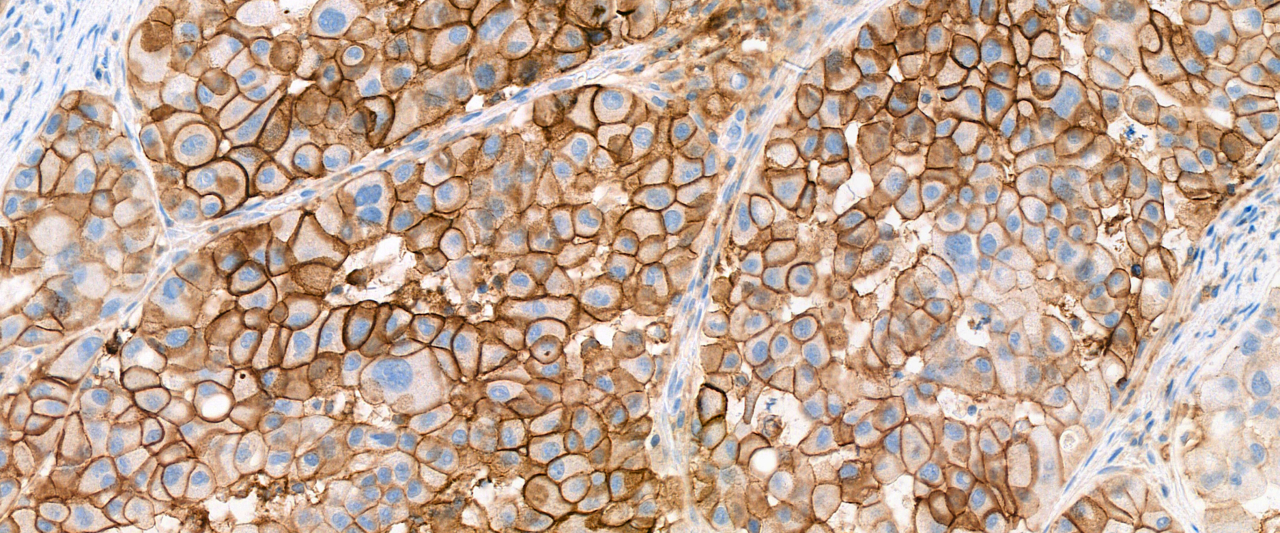

IHC-dag over Farmacomarkers

Enthousiaste sprekers geven op deze dag uitleg over immuun kleuringen in de diagnostiek in combinatie met therapie en behandelplan.